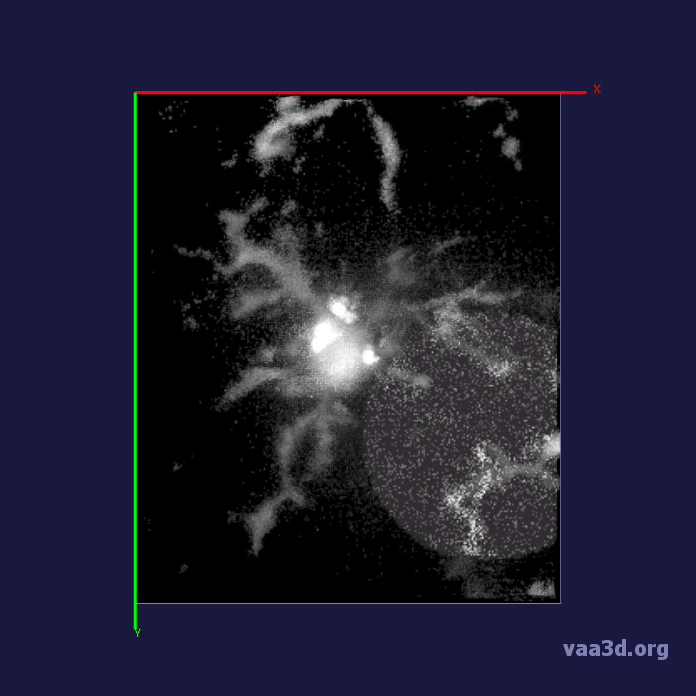

The 3D movies of microglia were imaged over 20 minutes with z-stacks taken at one minute intervals, containing single or multiple microglia per field of view. Some of the images were cropped from a larger field of view containing about 10 different cells and two images were imaged from a zoomed in view of one individual cell. The images ranged from a horizontal pixel width of .01 um and a vertical pixel width of .01 um to horizontal pixel width of .2 um and a vertical pixel width of .2 um. In the 3D images, there is variation in intensity contrast throughout the cell, non-structural noise, and fluorescence bleeding through z-stack due to the lengthy imaging technique which makes it difficult to visualize and process. The images were pre-processed using histogram equalization which increased the intensity throughout the cell but further increased noise in the background.

In our experiments, we compare the coupled TuFF-BFF microglia segmentation results with those given by L2S [21] and the Chan-Vese segmentation method [22]. The groundtruth in 3D was attained by manually tracing the object slice by slice from the z-stack. It must be noted that this was done by eye and could have some error. Figure 2 shows the visual comparison of the segmentation results for our dataset. Our result shown on the third column captures both the soma and processes. Figure 3 shows the Dice coefficient comparison of each segmentation method to the ground truth. Since the soma is much larger than the fine processes in the microglia, the processes have less volumetric impact on the similarity score. As explained in Section 1, segmenting the processes is important for quantifying the extension from the soma and its volume of surveillance. We use the Dice coefficient to quantitatively compare the ramification by taking the convex hull of the resulting segmentation. The Dice coefficient is a similarity measure that is computed using with where is the ground truth and is the compared image.

From Figure 4, the average Dice score for coupled TuFF-BFF was 0.77, compared to 0.53 for L2S [21] and .58 for Chan-Vese [22]. It must be noted that L2S required manual user initialization for each 2D image in the stack. While the Chan-Vese method has automatic seed selection, our coupled TuFF/BFF method was the only method that was a true 3D segmentation algorithm. L2S could not consistently capture the entire processes due to the intensity inhomogeneity throughout the object and background noise. The Chan-Vese segmentation could capture the extensions of the processes but did not work well with noise and attained false positives in the reconstruction. Since our method uses the tubular and blob information of the object to separate foreground and background, the segmentation only evolved within the object boundaries.